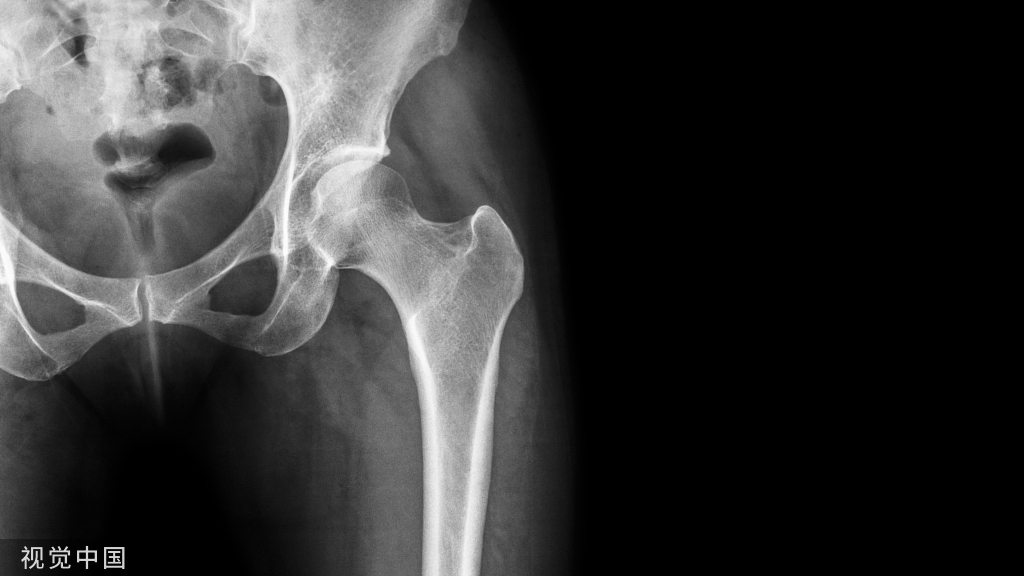

髂嵴、股骨大转子和坐骨结节是臀区最基本的骨性标志。臀襞儿近水平位,大致与臀大肌下缘相一致、稍斜向下外侧。